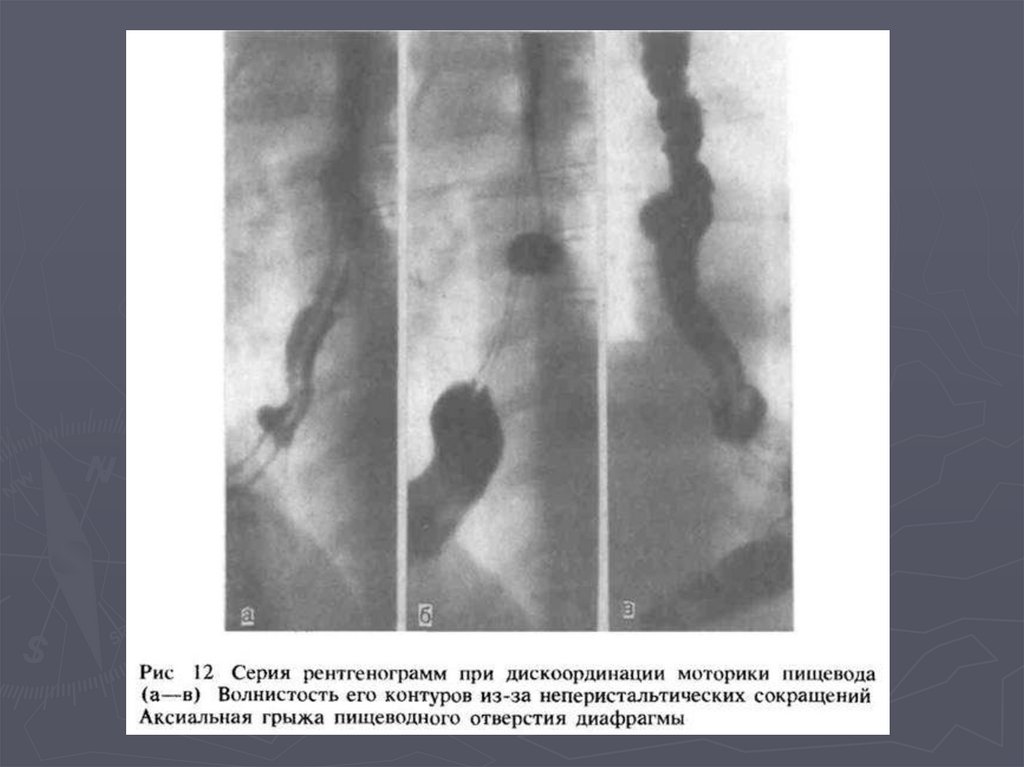

Грыжа пищеводного отверстия диафрагмы и обзор пищевода